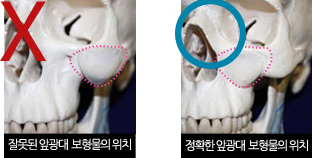

광대의 폭이 넓거나 돌출되지 않으면서도 눈 밑의 앞광대 부위가 볼륨이 없고 밋밋한 경우에는 상대적으로

옆광대가 나와 보이며, 눈 밑 부위가 전체적으로 꺼져 보이고 얼굴이 길어 보일 수 있습니다.

이러한 경우, 자가지방이식 또는 개인별 맞춤 보형물을 사용하여 보다 입체적이며 조화로운

얼굴형을 만들어 줄 수 있습니다.

입안 최소절개를 통해 다양한 크기, 모양의 보형물 중 개개인에 맞는 보형물을 사용합니다. 탑클래스 성형외과에서는

입안 최소절개를 통해 다양한 크기, 모양의 보형물 중 개개인에 맞는 보형물을 사용합니다. 탑클래스 성형외과에서는

Screw고정을 시행하여 근육의 움직임에 의한 보형물 이동을 예방하고 자연스럽고 어려 보이는 효과를 극대화시켜

줍니다.